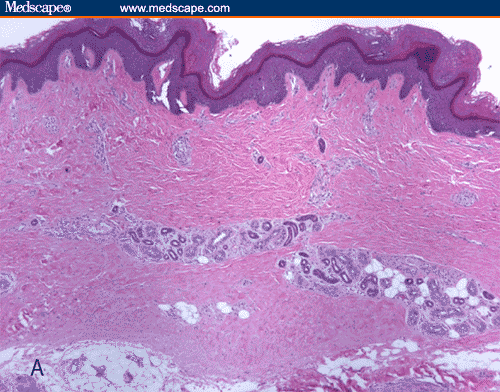

Scleroderma plaque fibrosis facial lesions

Scleroderma plaque fibrosis facial lesions 112 photos